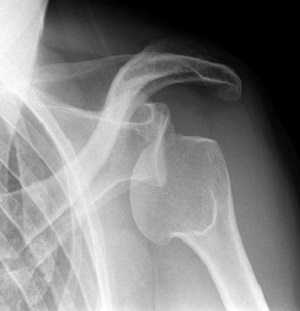

Самым важным методом исследования является рентген. Он проводится всем, у кого есть подозрение на вывих, потому, что дает возможность точно определить вид повреждения и предположить, какие могут быть последствия.

Врач не проводит вправление вывиха без рентгена. Его суть заключается в получении специальных изображений, на которых отображаются анатомические плечевые структуры. Лучи рентгена, когда проходят через организм, отчасти поглощаются, степень этого процесса зависит от типа органа и ткани. Чаще всего осуществляется рентген плеча в двух проекциях.

Для уточнения диагноза в соответствии с МКБ 10 и определения тактики лечения вывиха правого или левого плеча врач может назначить проведение КТ, МРТ, ультразвукового исследования. Так можно понять необходимость ношения бандажа, операции и так далее.